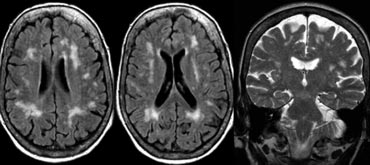

Fazekas scale for WM lesions

On MR, white matter hyperintensities (WMH) and lacunes - both of which are frequently observed in the elderly - are generally viewed as evidence of small vessel disease.

The Fazekas-scale provides an overall impression of the presence of WMH in the entire brain.

It is best scored on transverse FLAIR or T2-weighted images.

Score:

• Fazekas 0: None or a single punctate WMH lesion

• Fazekas 1: Multiple punctate lesions

• Fazekas 2: Beginning confluency of lesions (bridging)

• Fazekas 3: Large confluent lesions

The Fazekas scale for WM lesions predicts future disability in elderly. The Fazekas scale for WM lesions predicts future disability in elderly.

Fazekas 1 is considered normal in the elderly.

Fazekas 2 and 3 are pathologic, but may be seen in normally functioning individuals.

They are however, at high risk for disability.

In 600 normally functioning elderly people the Fazekas score predicted disability within one year (table). In the Fazekas 3 group 25% was disabled within one year (10).

Three year follow-up shows that severe white matter changes independently and strongly predict rapid global functional decline (17).